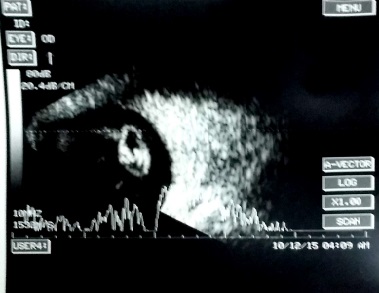

[The funnel RD is attached to the disc and is not showing after-movements with ocular movements.]